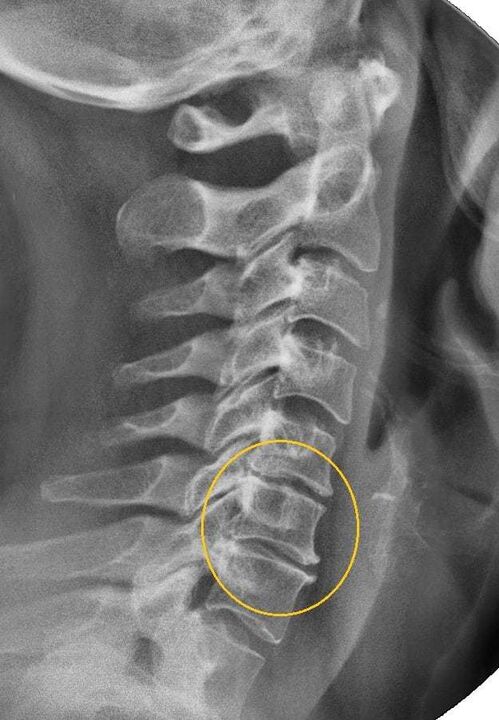

Stufe II

In diesem Stadium begann der Vorsprung der Wirbeltiere, die Bandbrandrisse schmal, die Kollagenfaser des faserigen Ringes der Scheibe wird zerstört. Aufgrund der Kompression der Nervenstämme, die sich während der Halsbewegungen und den Kopfwechsel intensiviert, gibt es spürbare schmerzhafte Symptome einer Punkt Natur. Hier können Sie bereits die zervikale Osteochondrose verdächtigen, deren Symptome im zweiten Stadium wie folgt sind:

Stufe III

Der faserige Ring in der Scheibe wird zerstört, Hernien werden gebildet. In der dritten Stufe gibt es aufgrund ihrer schwachen Fixierung eine Verformung der Wirbelsäule, Verschiebung und Versetzungen der Wirbel. Die Symptome sind wie folgt:

- Intensiv, akute Schmerzen im Nacken, Kragenzone, Herzbereich;

- die Empfindlichkeit der Kopfhaut auf dem Hinterkopf, in der Schulterregion, in den Händen bis zur völligen Abwesenheit;

- Hernie der Halswirbelsäule;

- Parese und Lähmung der oberen Extremitäten;

- Tenduläre Reflexe werden praktisch nicht beobachtet.

Dies ist ein schwerwiegendes Stadium der Krankheit, in dem der Patient seinen Kopf nicht mehr selbst unterstützen kann. Die Ischämie der Rückenmarks und die Kompression der Wirbelsäulenarterien führen zu Lähmungen und Parese in anderen Körperteilen und in den Wirbelsäulenstrich.